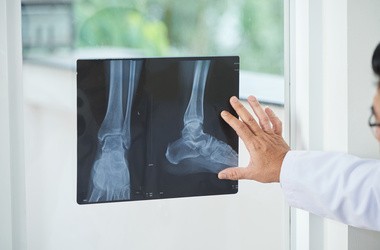

Endoproteza stawu kolanowego – przebieg operacji

- Zabieg przeprowadzany jest w znieczuleniu ogólnym. Przy zastosowaniu specjalnego mankietu dokonuje się chirurgicznego otwarcia stawu od przodu.

- Następnie resekcji poddaje się wszystkie patologiczne zmiany, które można usunąć.

- W dalszej kolejności, poprzez wykorzystanie stawu próbnego, dokonuje się oceny możliwości kolana oraz dobiera się najbardziej odpowiednią endoprotezę. Bardzo często na tym etapie może dojść do zmiany decyzji co do zakresu wymiany stawu.

- Po właściwej ocenie zostaje zainstalowany implant.

- Kiedy etap związany z samą wymianą elementów stawowych zostaje zakończony, zostają założone dreny, następnie lekarz zszywa tkanki.

- Po założeniu opatrunku pacjent zostaje przewieziony na salę pooperacyjną.